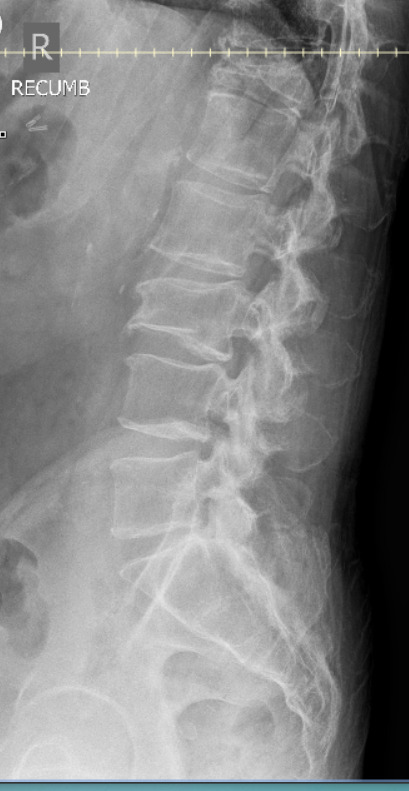

Radiographic examination of the cervical and lumbar spine identified adequate bone density, (decreased bone density cannot be identified on plain radiographs until more than 30-50% of bone mass has been lost3), cervical, lower thoracic and lumbar disc degeneration, and cervical and lumbar zygapophyseal osteoarthrosis.

Approximately 10 weeks later the patient reported injury to the low back while carrying a large, heavy object and stepping down, resulting in moderate, non-radiating pain with both rest and activity. Radiographic examination of the lumbar spine revealed a compression fracture of the inferior aspect of L3 with step defect, possibly acute, and ununited left L2 and L3 transverse processes, age indeterminate. The patient was referred for DEXA bone density examination and cross-sectional imaging (CT) to further evaluate the extent of the L3 compression fracture.

Chiropractic care using Thompson drops in unaffected spinal regions continued for the next 5 weeks. After a 7-month absence from care, the patient returned reporting midline and centrally worsening non-radiating low back pain after a fall on his back and buttocks approximately 3-4 months prior in his bathroom. He was seen by his medical doctor prior to the treatment visit for this incident and had been referred to physical therapy. He denied head injury, fracture, loss of consciousness, saddle paresthesia or changes with bowel and bladder function. Radiographic examination of the lumbar spine demonstrated superior and inferior endplate fractures of the T12 vertebral body with 60% vertical loss of height not evident on previous examination. Osteoporosis was reported at this time. Examination with CT and MRI were recommended for further characterization of the T12 compression fracture due to the severity of radiographic presentation. The patient was referred to his primary care physician for co-management and the provider was contacted directly due to the loss of vertebral body height (see Table 1 for overview of progression of care).